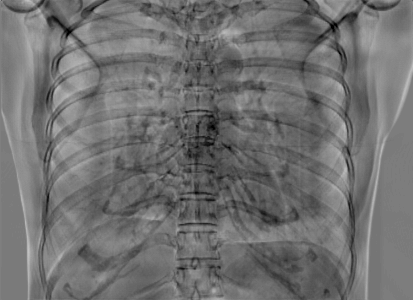

5.1 Chest Data

Refer to caption

(a) Reference

(b) 0superscript00^{\circ} perspective

(c) (b)-(a)

0.4237, -, -

0.4002, 17.01, 0.6532

Pix2pixGAN

(d) 0superscript00^{\circ} Cartesian

(e) 0&180superscript0superscript1800^{\circ}\&180^{\circ} Cartesian

(f) 0&180superscript0superscript1800^{\circ}\&180^{\circ} polar

0.4303, 7.08, 0.8535

0.4214, 5.37, 0.9098

0.4240, 3.83, 0.9536

(g) (d)-(a)

(h) (e)-(a)

(i) (f)-(a)

TransU-Net

(j) 0superscript00^{\circ} Cartesian

(k) 0&180superscript0superscript1800^{\circ}\&180^{\circ} Cartesian

(l) 0&180superscript0superscript1800^{\circ}\&180^{\circ} polar

0.4272, 10.92, 0.8222

0.4281, 9.37, 0.8424

0.4248, 8.12, 0.8859

(m) (j)-(a)

(n) (k)-(a)

(o) (l)-(a)

Figure 10: Perspective deformation learning in one exemplary patient case for chest X-ray imaging. The maximal horizontal cardiac diameter and the maximal horizontal thoracic diameter in (b) and (d)-(f) are indicated by the horizontal red lines, while those in the reference image (a) are green lines. The cardiothoracic ratio, RMSE, and SSIM for each image is displayed in its corresponding subcaption.

The results of one patient in chest X-ray imaging are displayed in Fig. 10, where the cardiothoracic ratio is assessed as an exemplary clinical application [32]. In the reference image (Fig. 10(a)), the maximal horizontal cardiac diameter (MHCD) and the maximal horizontal thoracic diameter (MHTD) are indicated by two green horizontal lines. Its cardiothoracic ratio is 0.4237. In the 0superscript00^{\circ} perspective projection image (Fig. 10(b)), all the anatomical structures can be visualized with fine resolution. However, due to perspective deformation, anatomical structures, e.g. the ribs and the spine, are deformed. The deformations are visualized better in the difference image Fig. 10(c). Compared with the ribs and the spine, the heart has less deformation as its location is closer to the isocenter. In Fig. 10(b), the MHCD and the MHTD are indicated by two red horizontal lines, while the green lines are those of the reference image. While the MHCD has changed little from 10.47 cm to 10.16 cm, the MHTD has changed considerably from 24.71 cm to 25.40 cm. As a consequence, the cardiothoracic ratio becomes 0.4002, which is below the normal range of 0.42 - 0.50 [32]. The result of learning perspective deformation from 0superscript00^{\circ} single view is displayed in Fig. 10(d), where the MHCD and the MHTD are 10.63 cm and 24.71 cm, respectively. The MHTD of Fig. 10(d) is the same as that of the reference image. This is also reflected by the difference image Fig. 10(g), where the lower ribs have small errors. However, the upper ribs as well as the spine still have considerable errors. The results of perspective deformation learning from 0&180superscript0superscript1800^{\circ}\&180^{\circ} views in Cartesian and polar coordinates are displayed in Fig. 10(e) and Fig. 10(f), respectively. The measured MHCDs and MHTDs in these two images are very close to the reference ones. Hence, their cardiothoracic ratios, 0.4214 and 0.4240 respectively, are close to the reference ratio as well. In the difference images (Fig. 10(h) and Fig. 10(i)), the errors of ribs and spine decrease as their boundaries are no longer apparently visible. Nevertheless, Fig. 10(i) has less error than Fig. 10(h), achieving the smallest RMSE value of 3.83. The quantitative evaluation of all the 162 testing datasets is displayed in Tab. II, where learning perspective deformation from two complementary views in polar coordinates achieves the least RMSE 4.98 and highest SSIM 0.9517, demonstrating the superiority of learning perspective deformation from two complementary views in polar coordinates.

The TransU-Net results are displayed in Figs. 10(j)-(l). Compared with their corresponding Pix2pixGAN results, the TransU-Net prediction images are more blurry, although the same perceptual loss is used. The error images in Figs. 10(m)-(o) indicate that TransU-Net reduces perspective deformation better with complementary views than a single view. The quantitative evaluation in Tab. II shows that TransU-Net cannot effectively reduce perspective deformation with a single view. With complementary views in both Cartesian and polar coordinate systems, TransU-Net achieves comparable performance, which is still considerably worse than that of Pix2pixGAN. The inferior performance of TransU-Net to Pix2pixGAN on the chest data is potentially caused by the repetitive nature of the segmental rib anatomy, which leads TransU-Net to be ineffective in extracting position-dependent features.